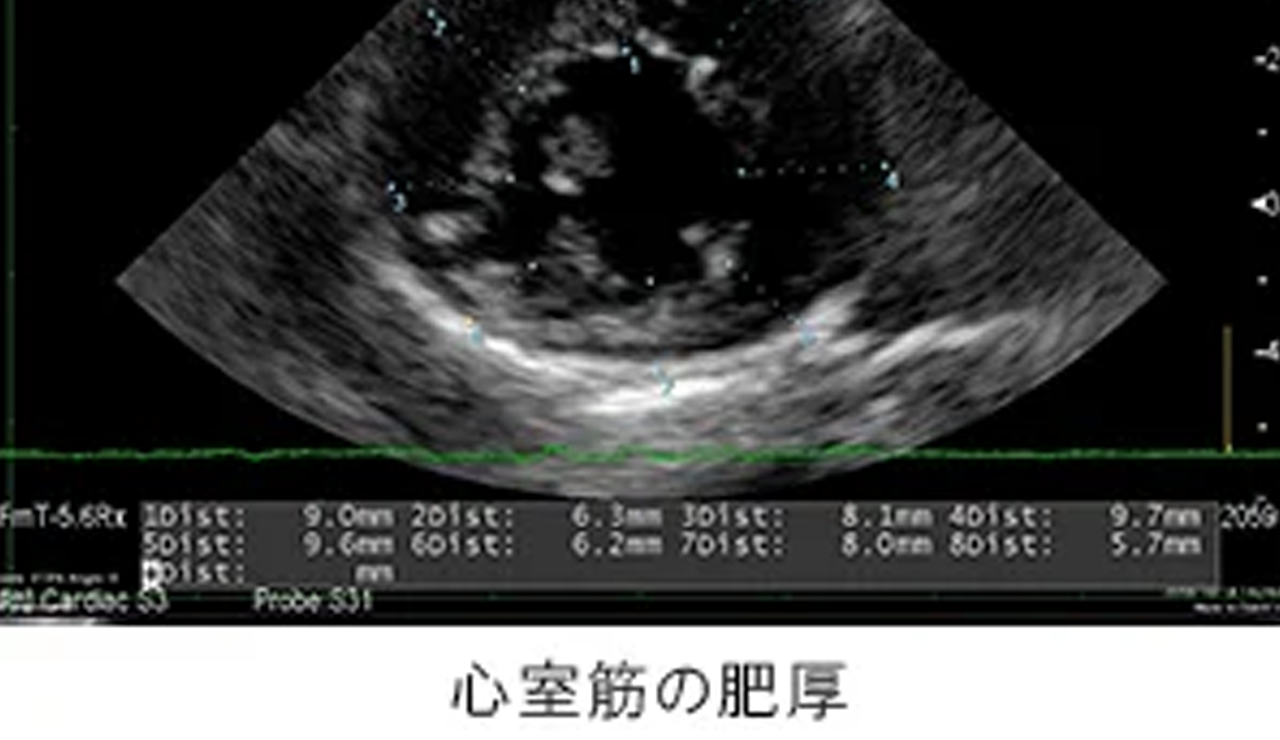

初期には症状が出ないことも多く、精密検査ではじめて発見に至ることも多い動物の心臓病。年齢とともに罹患率も高まり、重篤化しやすいため、定期的な診察を通じて早期発見・早期治療を心がけましょう。

ピジョン動物愛護病院では、各院いずれもレントゲン検査や最新の超音波検査装置による心臓の精密検査を実施しています。

| 動物の小さな心臓の動きが詳細に評価可能な検査装置。 心臓内における血液の速度や方向、弁膜の構造を痛みを伴うことなく評価でき、正確な診断と治療を可能にします。 |